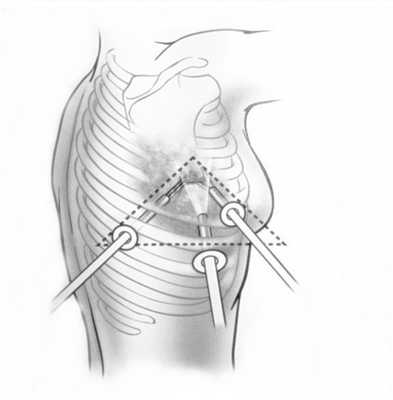

Поскольку тактика лечения лимфомы средостения определяется гистологическим и иммуногистохимическим типом опухоли, то обязательным этапом диагностики является биопсия. При увеличении доступных для пальпации лимфоузлов проводят эксцизионную, пункционную или прескаленную биопсию. В остальных случаях прибегают к операционной биопсии с помощью медиастиноскопии, парастернальной медиастинотомии, диагностической торакоскопии.

При невозможности получить образец ткани для исследования эндоскопически применяются инвазивные методы: трансторакальная биопсия, медиастиноскопия, видеоторакосокпия. Последние два метода — это серьезные операции, которые проводятся в специализированных медицинских учреждениях.